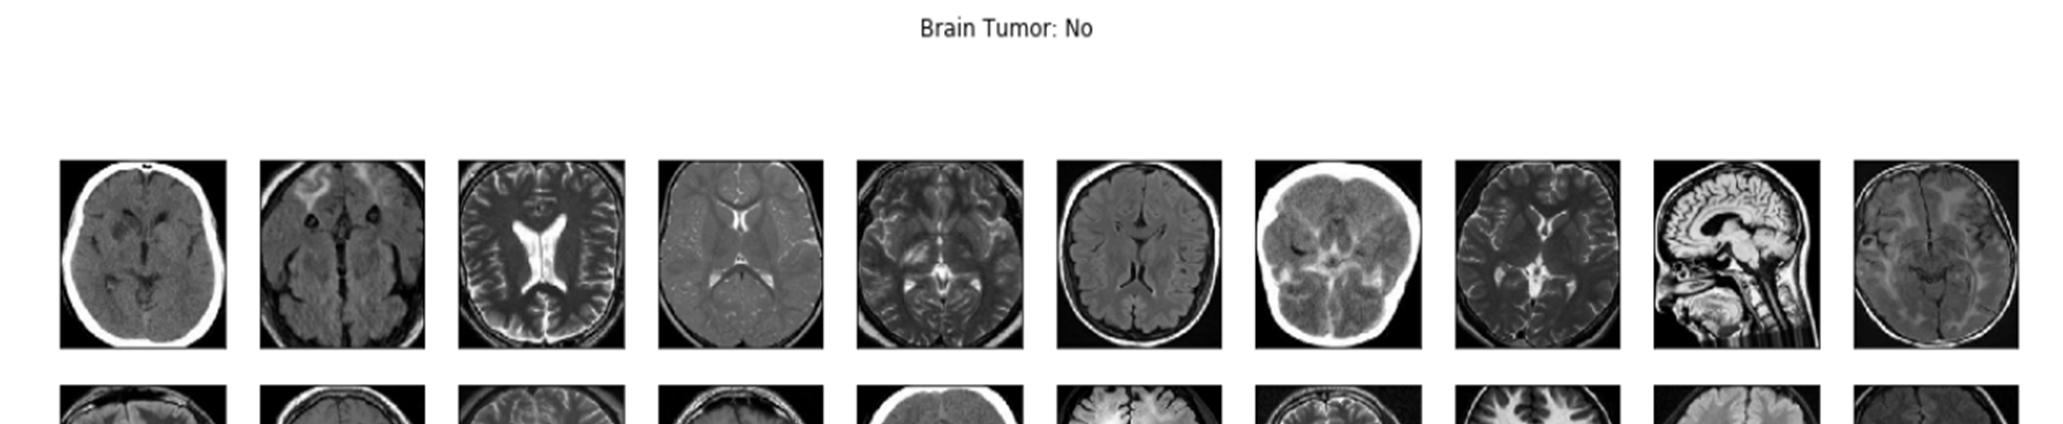

Figure1:Dataset of MRI scans containing no tumors

The Database was gathered from Kaggle, named ‘Brain MRI Images for brain tumor Detection’ By Navoneel Chakrabarty.[6] The dataset comprises 253 Brain MRI Images in the folders yes and no. The folder yes contains 155 timorous brain MRI images, whereas the folder no has 98 non timorous brain MRI images.

Data augmentation is a technique used in data analysis to expand the volume of information by inserting reproductions of pre existing data that have been significantly altered or newly created synthetic data from preexisting data. Before data augmentation, the dataset contained 155 positive and 98 negative samples, producing 253 sample pictures. After data augmentation, a new dataset is created with 2065 example photographs from 1085 positive and 980 sample photos.